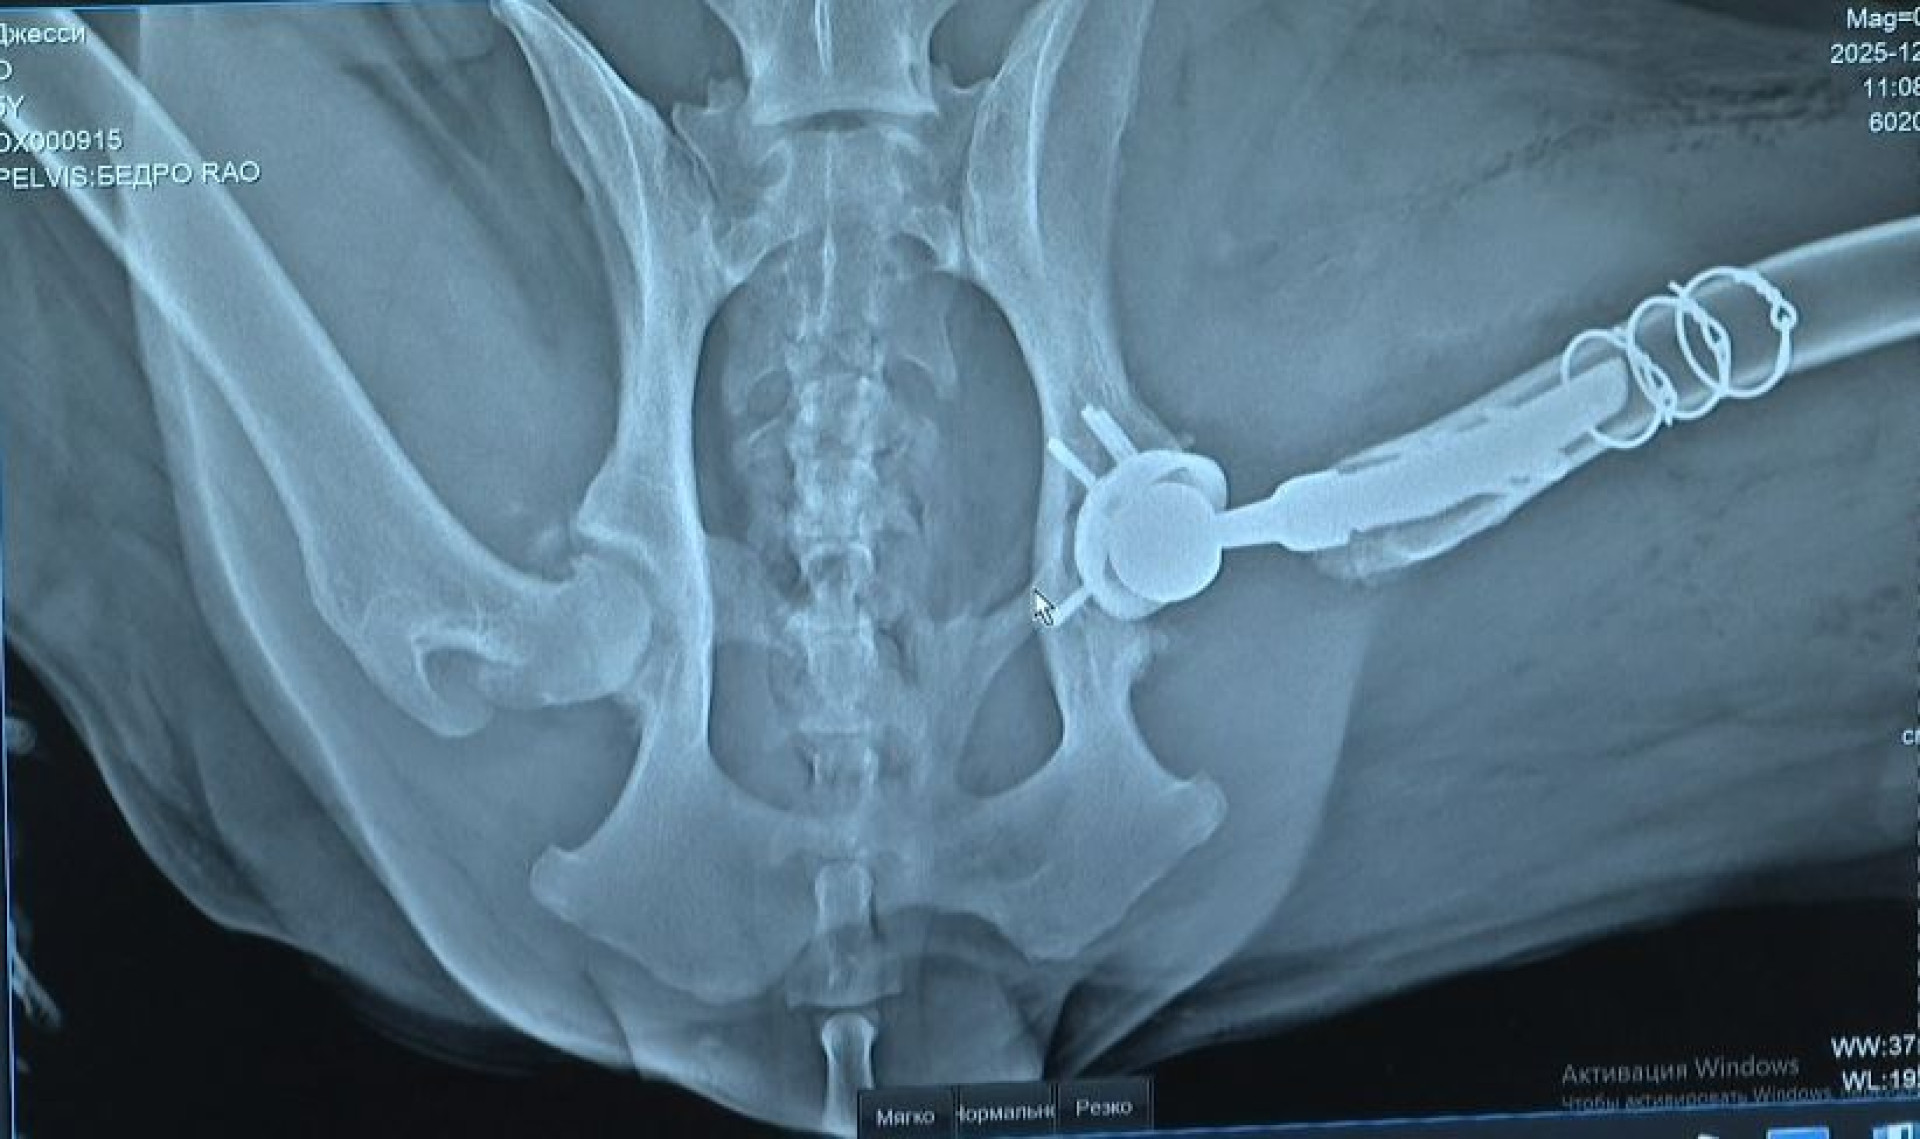

Первой пациенткой стала шестилетняя немецкая овчарка Джесси. С рождения у нее была дисплазия тазобедренного сустава, которая со временем переросла в артроз.

Операция длилась около четырёх часов. Для Джесси изготовили индивидуальный титановый протез на заказ.

Такой имплант может служить животному всю жизнь при правильном уходе.